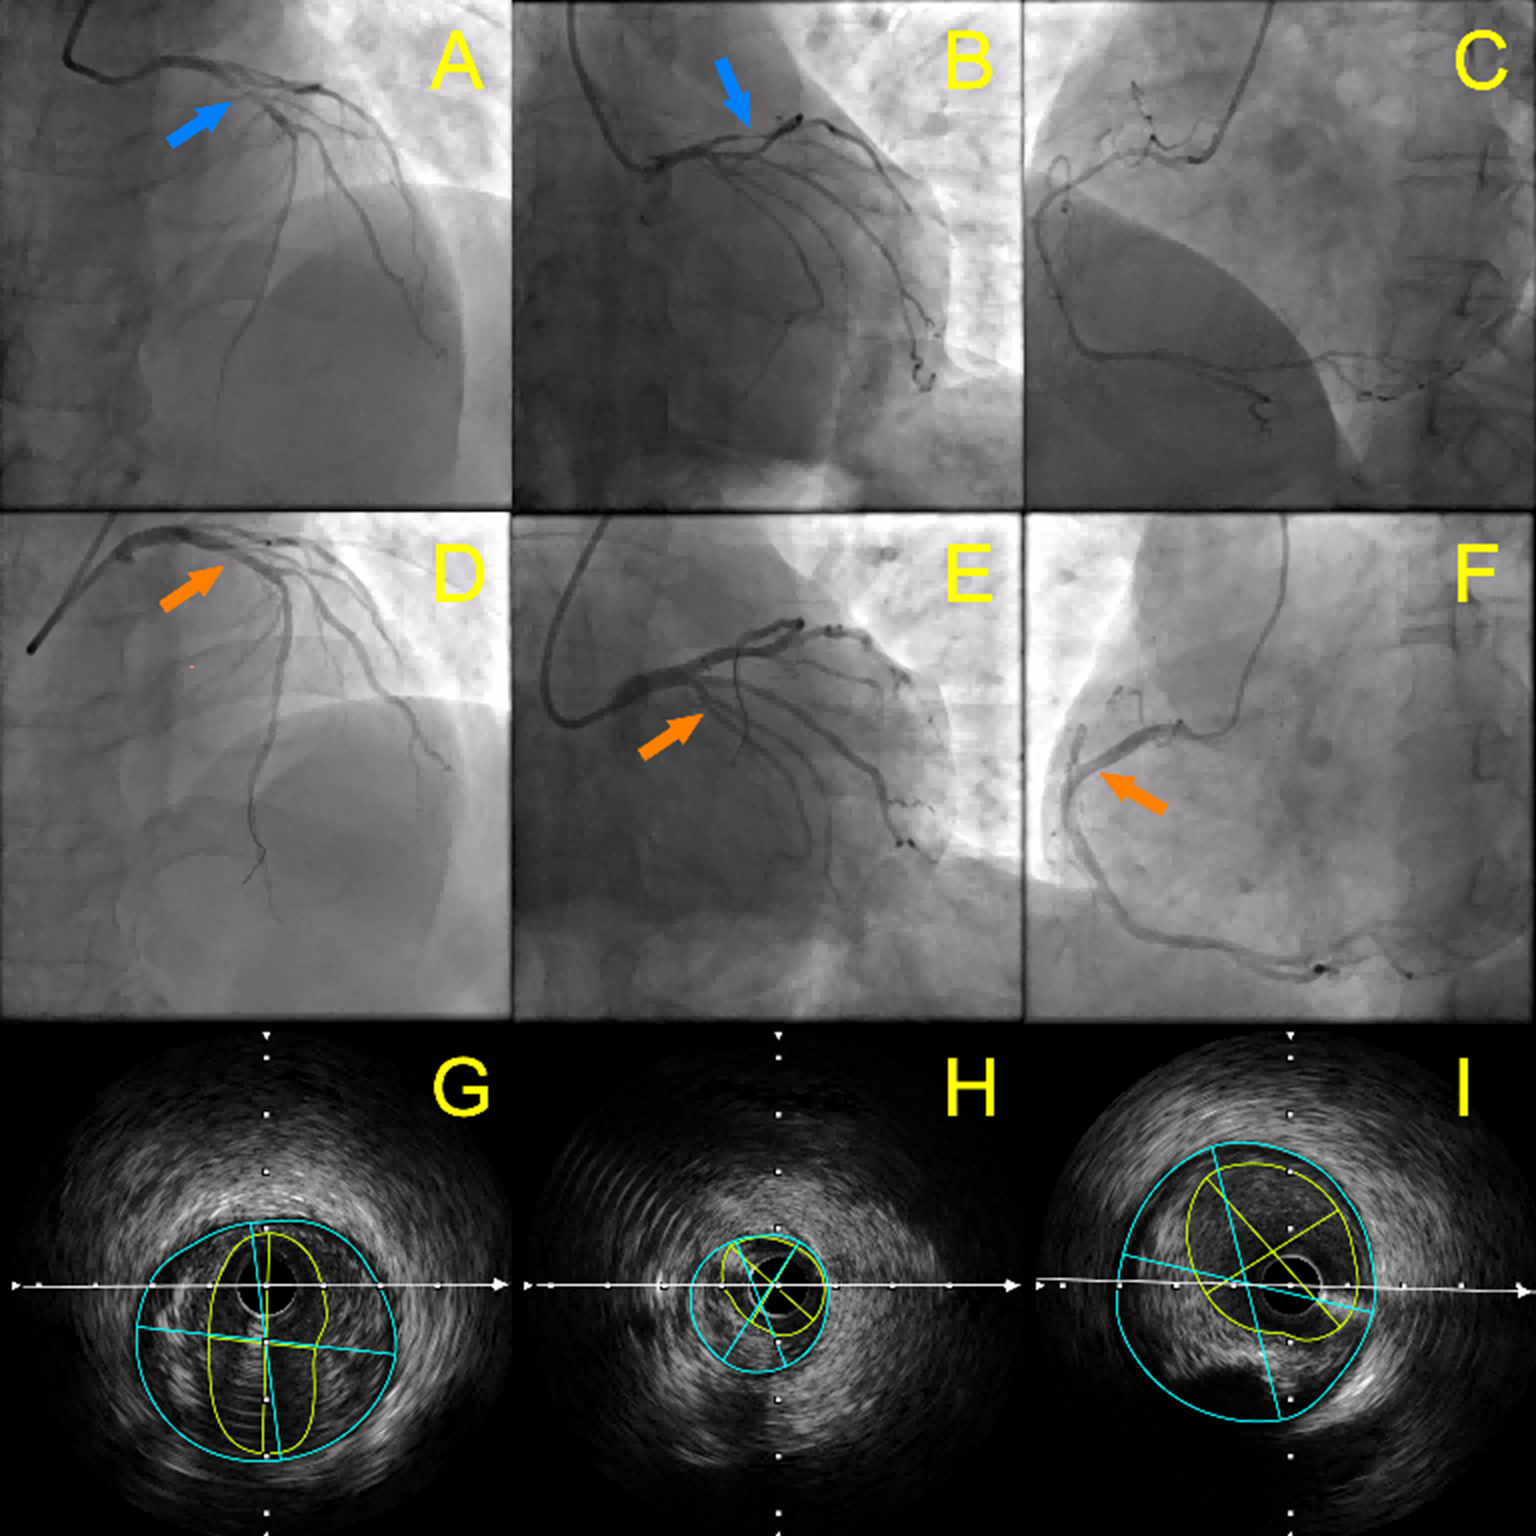

Emergency coronary angiography performed 2 hours after hospitalization showed that all coronary arteries were thin except for the left main trunk, with approximately 90% stenosis in the proximal segment of the left anterior descending artery (LAD) (Figure, A & B; blue arrows), multiple mild to moderate stenoses in the proximal and middle segments of the left circumflex artery (LCX) and obtuse marginal (OM), and moderate to severe stenoses in the proximal and middle segments of the right coronary artery (RCA) (Figure, A-C).

After intracoronary injection of 200 μg of nitroglycerin into the left coronary artery (LCA), the LCA became thicker than before and only mild stenosis remained in the proximal segment of the anterior descending branch (Figure, D & E), which we considered to be a multi-branch diffuse coronary spasm. Postoperatively, diltiazem, isosorbide mononitrate, atorvastatin, aspirin, and clopidogrel were administered, and the patient had no further episodes of chest tightness and chest pain. The coronary angiography on the fifth day of admission showed that the RCA diameter was also significantly thicker than before (Figure, F).

Intravascular ultrasound (IVUS) showed that the proximal segment of the anterior descending branch had a minimum lumen area of 6.42 mm2 with 57% plaque load (Figure, G), the proximal segment of the LCX had a minimum lumen area of 2.34 mm2 with 49% plaque load (Figure, H), and the middle segment of the right coronary had a minimum lumen area of 7.24 mm2 with 58% plaque load (Figure, I).